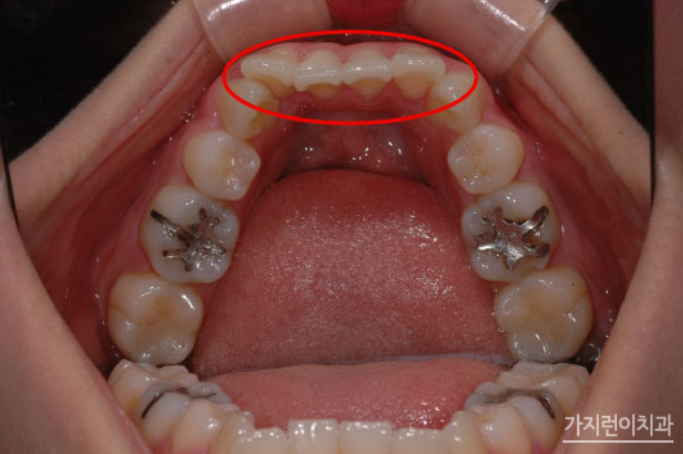

위 케이스는 돌출입 교정을 진행했지만 옥니로 변해버린 치아 케이스인데요. 돌출입 재교정은 실패 원인을 정확하게 파악하고, 해당 문제를 바로잡아야 하기에 보다 세세하게 환자 상태를 파악할 수 있는 진단 장비를 갖추고 있어야 합니다. 또한 의료진이 충분한 임상 경험을 가지고 있어야 하죠. 해당 분의 경우 돌출입 교정을 받았지만 개선 정도가 미비했으며 치열은 가지런해졌지만 과도한 교정력에 의해 하악 앞니가 옥니 형태가 되었다는 점이었습니다.

옥니는 전방의 치아가 안쪽으로 기울어져 들어간 형태를 말합니다.큰 불편함을 느끼지 못하기 때문에 방치하는 분들이 많이 계시지만 시간이 지나면 증상이 심화되어 결국 앞니로 음식을 끊어먹지 못하는 상황이 생기고 맙니다.